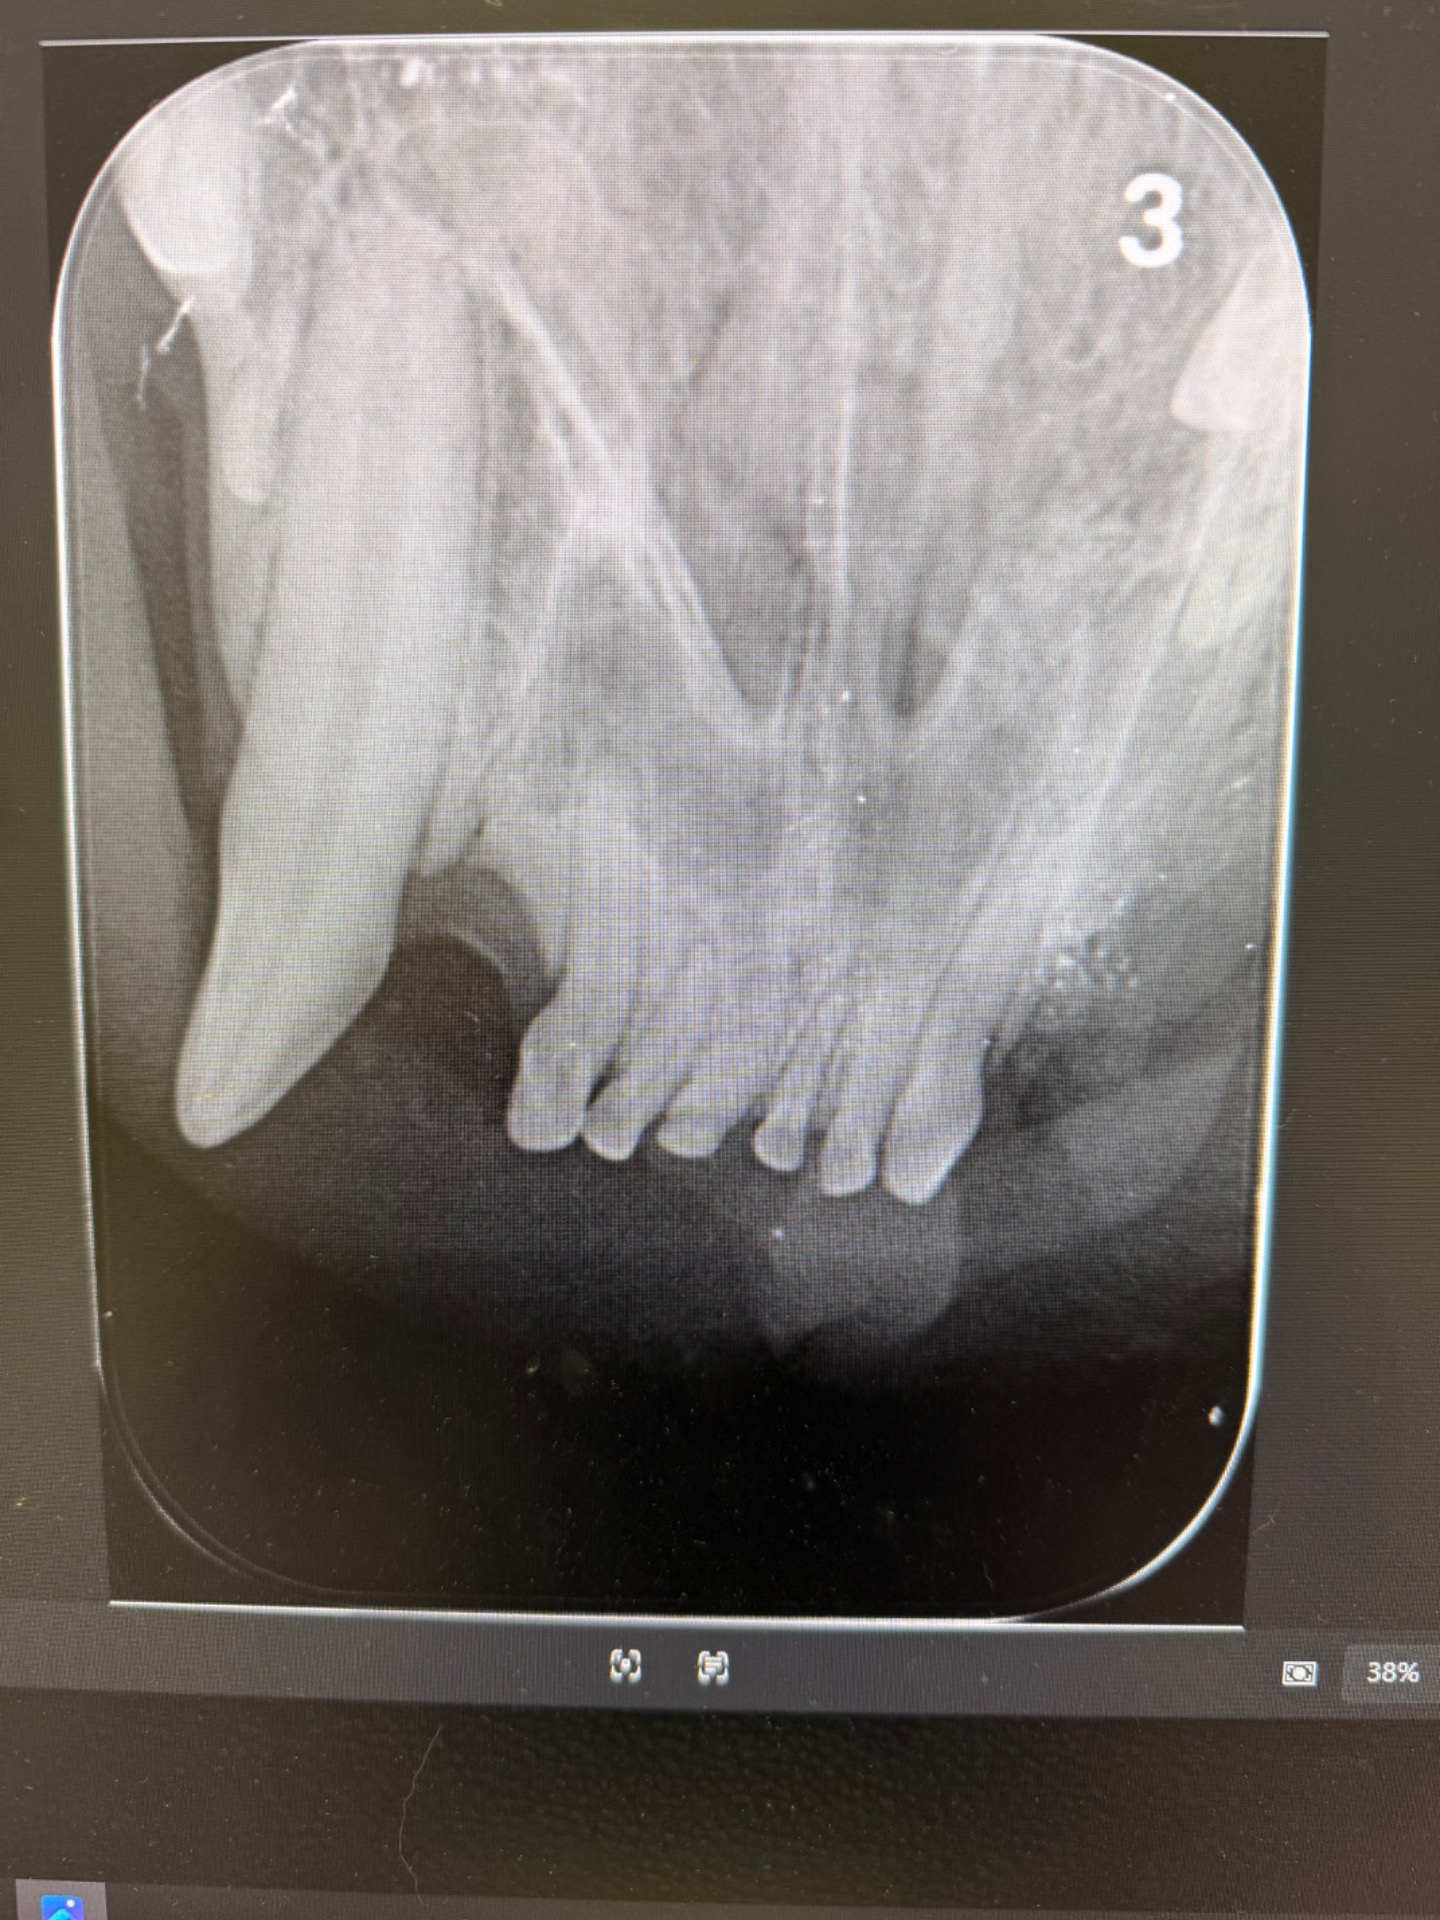

Fogászati RTG